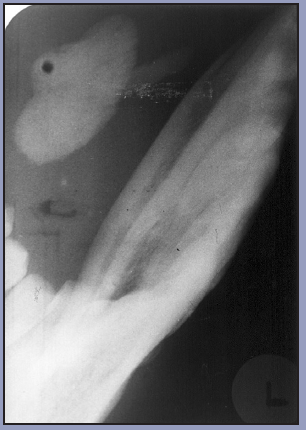

The occlusal image, as seen in Figure 3, is very useful in determining the buccolingual extension of pathologic conditions, and provides additional information as to the extent and displacement of fractures of the mandible and maxilla. Occlusal radiographic images also aid in localizing unerupted teeth, retained roots, foreign bodies, and calculi in the submandibular and sublingual salivary glands and ducts. It should be noted that when imaging soft tissues, exposure time needs to be appropriately reduced.

Figure 3 – Occlusal Images

Figure 3